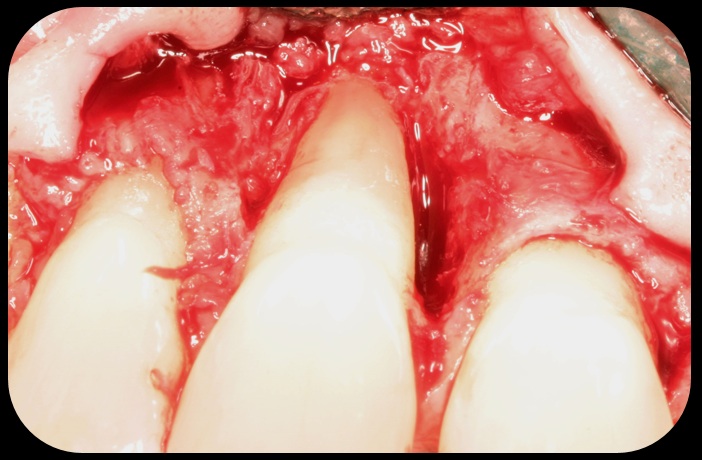

Facial bone loss and a mesial vertical defect.

Fig. 3

Then, too, are opportunities to prepare the site for regeneration by coupling therapies, applying an enamel matrix derivative, along with traditional bone grafts of demineralized freeze-dried bone allograft; potentially, gains in attachment with minimal probing depth and retained papilla may avoid the need for an implant (Figure 2 through Figure 7).